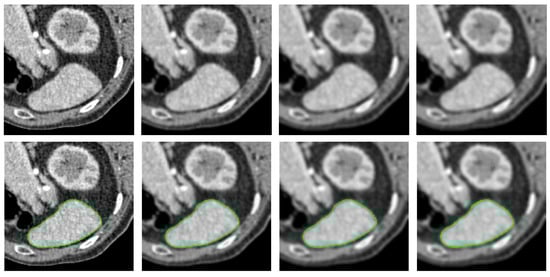

- The PolarMask model does not incorporate contour regularization. In scenarios where image quality is low or distorted by noise, such as in medical CT images, the absence of regularization can lead to unexpected and irregular segmentation results, highlighting significant room for improvement.

- Medical Images: For medical images, we select X-ray computed tomography (CT) scans from [41]. This dataset is commonly used in medical image segmentation evaluations, with image resolution ranging from to pixels, depending on the specific context of each test.

4.2. Qualitative Comparison Analysis

4.5. Performance Under Adverse Conditions